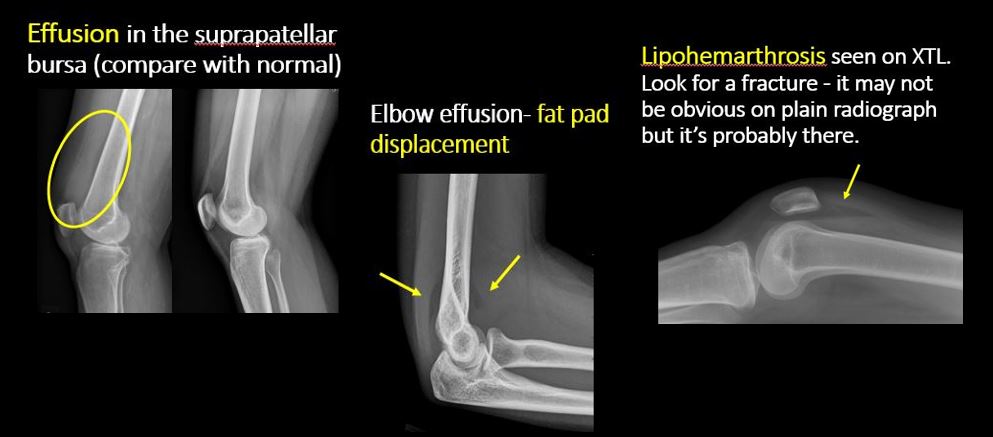

There is an effusion, fat pad displacement, or fat fluid level. |